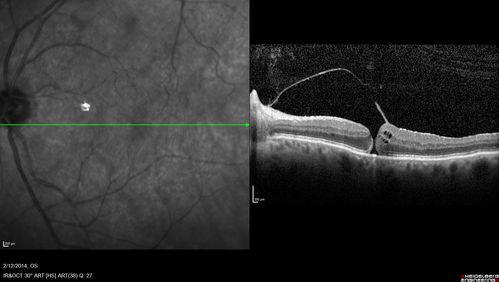

Macular Hole Left Eye - progression from VMT - Stage II macular hole - Spontaneously Closed Macular Hole

Vision has dropped to 20/50 and there is a full thickness macular hole